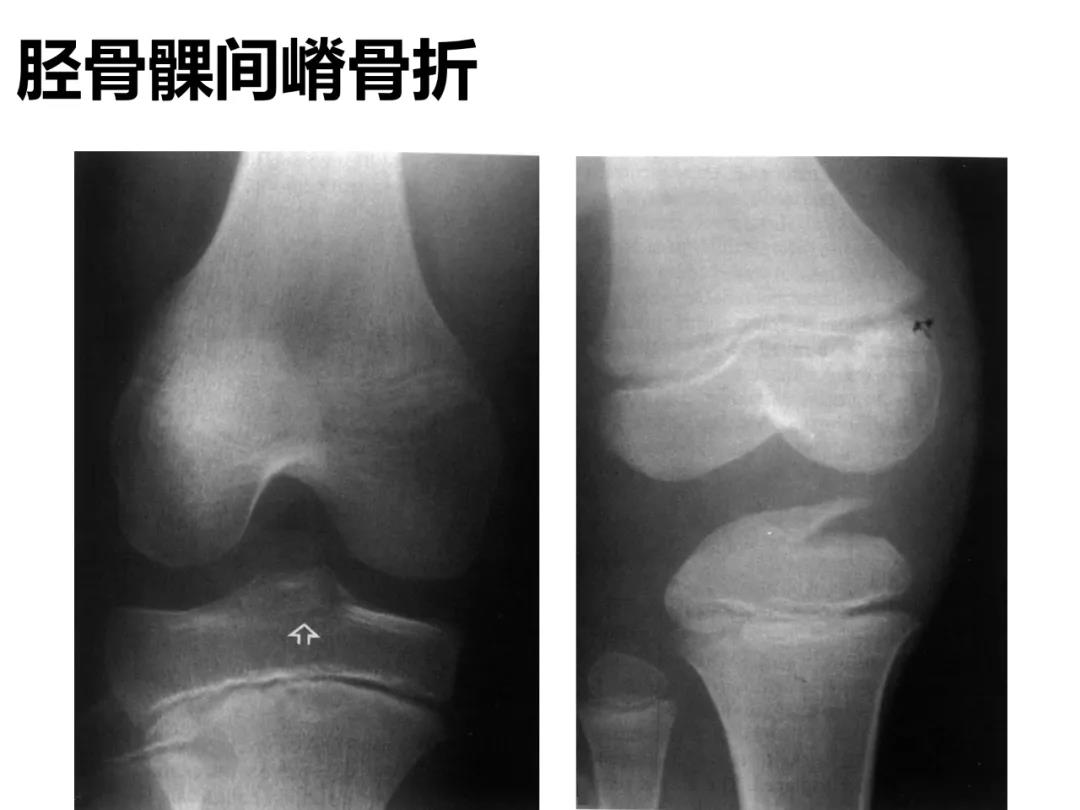

小儿骨科X线片汇总,临床读片宝典!